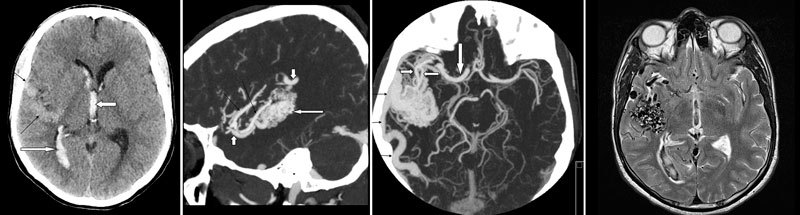

Hægt er að greina æðaflækjur með tölvusneiðmyndaæðarannsókn, segulómskoðun (SÓ) og SÓ-æðarannsókn og hefðbundinni æðamyndatöku (conventional catheter angiography) (mynd 1abcd). Hefðbundin tölvusneiðmynd er næm til greiningar á bráðri heilablæðingu en varpar ekki fullnægjandi ljósi á æðaflækjuna sjálfa. Leggja verður áherslu á að hefðbundin tölvusneiðmynd útilokar ekki æðaflækju. Tölvusneiðmyndaæðarannsókn sýnir æðaflækjur með skýrum hætti og hefur yfirburði yfir segulómæðamynd. Segulómskoðunin gefur þó betri mynd af tengslum æðaflækju og aðlægs heilavefs.2 Hefðbundin æðamyndataka (conventional angiography) er kjörrannsókn þegar kemur að því að gefa sem skarpasta mynd af uppbyggingu æðaflækjunnar, til að sýna fram á tilvist æðagúls og kortleggja bláæðafráflæðið. Æðaflækjur geta breyst og stækkað með tímanum. Þeim breytingum má fylgja eftir með myndrannsóknum.